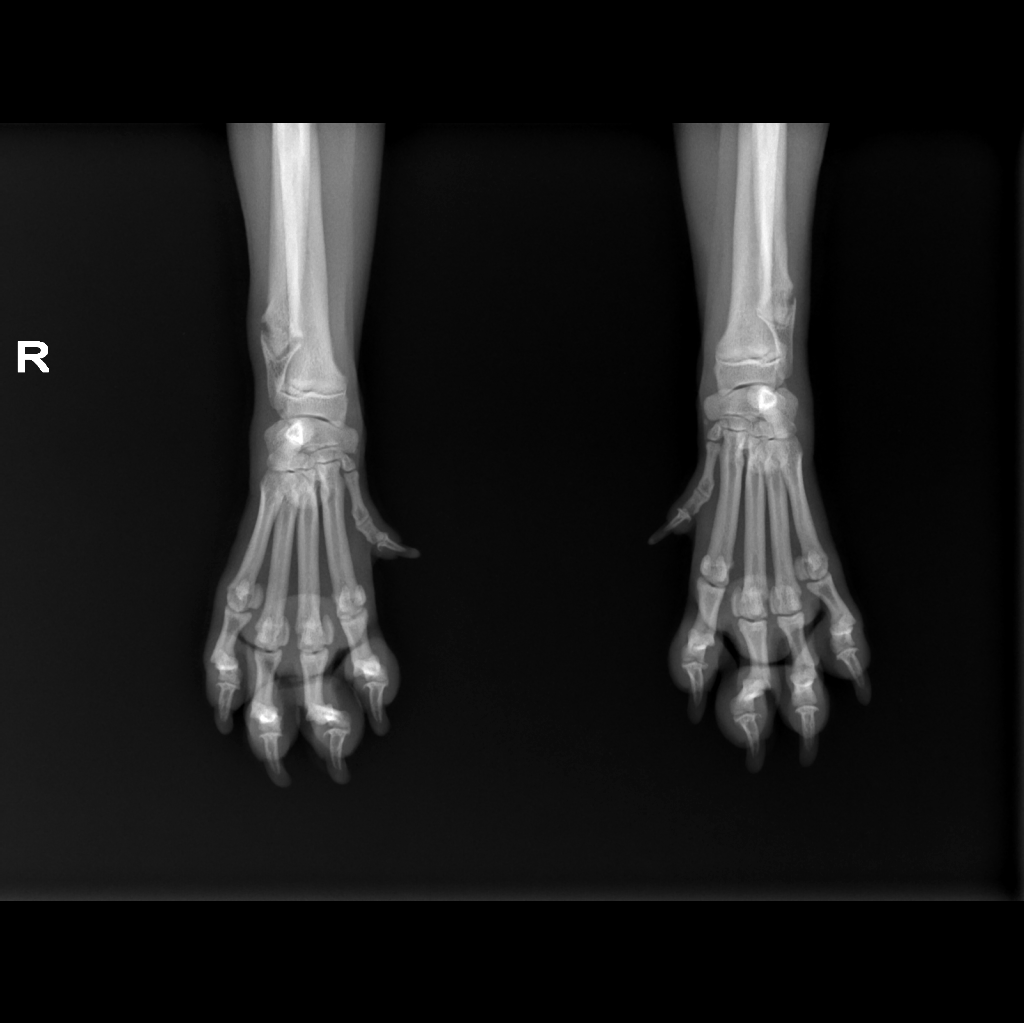

Male, 7 months old, 5 kg Pug dog

Orthopedic examination reveals bilateral carpus valgus, more evident on the left forelimb,

Radiographic exam and CT scan of forelimbs was performed

Diagnostic imaging reveal bone density alterations affecting the distal ulnar physis, bilaterally, characterized by bone rarefaction, retention of the cartilaginous core and irregular ossification.